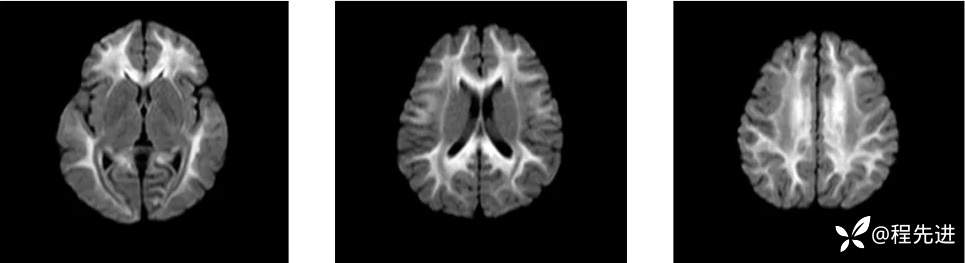

MRI: